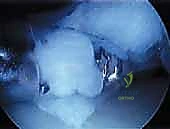

الخطوة 3: استكشاف المفصل بالكاميرا 4K

يتم إدخال كاميرا دقيقة متصلة بشاشة 4K عالية الوضوح داخل الركبة. تتيح هذه التقنية للدكتور هطيف رؤية المفصل من الداخل بوضوح يفوق الرؤية بالعين المجردة، مما يسمح بتقييم حجم الغضروف القرصي، نوعه، ومكان التمزق بدقة.

الخطوة 4: تصغير الغضروف وإعادة التشكيل (Saucerization / Meniscoplasty)

هذه هي الخطوة الأهم. الهدف ليس إزالة الغضروف بالكامل (كما كان يحدث في الماضي مما يؤدي لخشونة مبكرة)، بل إعادة تشكيله. باستخدام أدوات ميكروسكوبية دقيقة، يقوم الدكتور هطيف بقص الأجزاء الزائدة من الغضروف من المنتصف، محولاً إياه من شكل القرص (O) إلى شكل الهلال الطبيعي (C). هذه العملية تسمى (Saucerization).

الخطوة 5: إصلاح التمزقات والتثبيت (Meniscal Repair)

- إذا كان هناك تمزق في الجزء المتبقي من الغضروف، يتم خياطته وإصلاحه باستخدام خيوط طبية خاصة تذوب بمرور الوقت.

- في حالة نوع وريسبيرغ (Wrisberg): حيث يكون الغضروف غير متصل بالكبسولة الخلفية، يقوم الدكتور هطيف بإجراء تقنية متقدمة لتثبيت الغضروف في مكانه الطبيعي باستخدام غرز جراحية دقيقة، مما يمنع الطقطقة وعدم الاستقرار نهائياً.